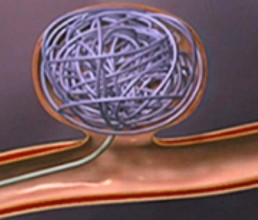

Two main treatment options exist: Endovascular coiling of aneurysms (where a catheter is inserted through arteries under x-ray guidance and tiny platinum based coils are placed inside the aneurysm), and open surgical clipping of aneurysms.

These devices include stents (wire tubes which line the vessel walls an allow treatment of aneurysms which would otherwise be unfavourable for coiling alone).